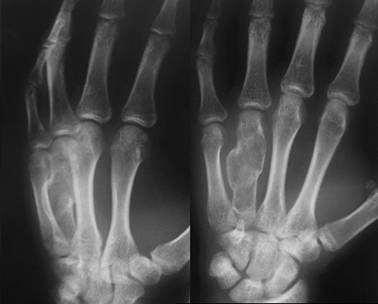

Хондрома кисти